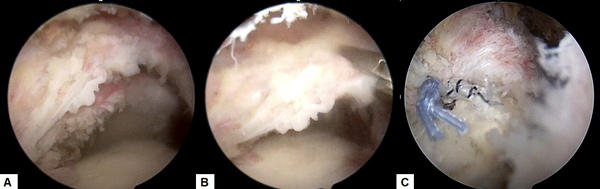

肩の痛みは外来で遭遇する頻度の高い症状です。多くは肩関節周囲炎(いわゆる四十肩・五十肩)によるものですが、一部には肩関節の周囲に存在する腱板という組織が損傷していることにより痛みが出ている場合があります(腱板断裂または損傷)。加齢性の変化で切れる場合や、外傷性の場合、また肩を使う仕事やスポーツなどにより摩耗して切れる場合があります。保存治療を行なっても痛みが続く場合、関節鏡を用いた腱板の修復術が行われます。

A: 腱板断裂部(上に見えているのが断端。下に上腕骨が見えている(黒丸部)。)

B: 断裂部を鉗子(右上)で牽引している。

C: 特殊な糸を用いて断裂部を上腕骨に縫着した(左側に青と白黒縞模様の糸による結び目が見えている)。